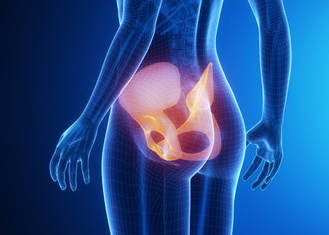

엉치뼈 통증은 가벼운 스트레칭으로도 완화시킬수있습니다.

엉덩이 뼈가 심하게 아파프다고 휴식만 취하시면 안 되고, 힘들어도 가끔씩 간단하게라도 스트레칭을 해주셔야 됩니다.

곧은 자세에서 몸을 가볍게 털고, 허리를돌리고 다리 근육을 풀어주면서 온몸을 늘려주는 스트레칭하는 것은 앉을 때 엉치뼈 통증을 없애는 아주 좋은 방법입니다.

엉치뼈 통증이 심한 날에는 반신욕으로 엉덩이 주변의 근육을 풀어주는 것도 매우 좋은 방법입니다.

엉치뼈 통증 완화

또한 엉치뼈 통증을 제거하기 위해서는 발 쪽으로 가는 혈액을 상체로 혈액을 이동하는 것이 좋은데요. 그래서 휴식을 취하면서 다리를 올린 채 누우면 엉치뼈의 통증이 완화되며 통증제거 방법으로 굉장히 좋습니다.